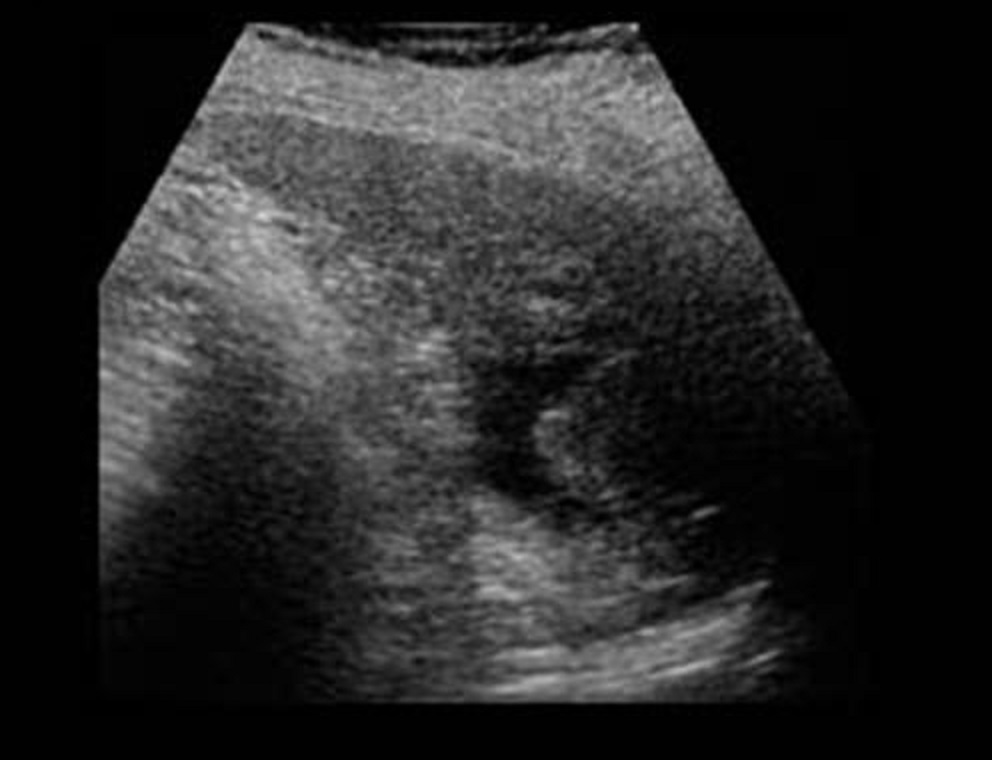

Image

echographique d'une traumatisme de la rate agrave a

grade II avec hematome sous capsulaire ( fleche

blanche ) et quelque zone de hypoechogene mal limite

intra parenchymateuse de la rate . |

Traumatisme de la rate grave ( grade IV ) avec

hematome intra parenchymateux marque ( fleche

blanche ) et dechirure capsulaire avec saignement

hilaire . Image de hemoperitoine localise a

inferieure de la rate peut en s'observer . Image

echographique en coupe longitudinale |